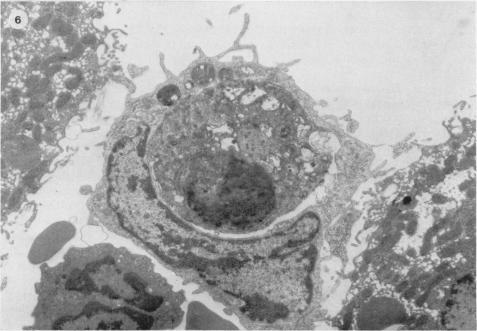

The i.v. administration of suspensions of beryllium phosphate (5-50 mumol/kg) to rats resulted in the vacuolation of hepatic Kupffer cells within 3 h. After 6 h necrotic Kupffer cells were common throughout the sinusoids of the liver but no changes were detected in the hepatic parenchymal cells during this period. A significant reduction in the numbers of intrasinusoidal cells was observed 14 h after treatment but this population had reverted to normal within 24 h. The administration of colloidal carbon to treated animals at this time did, however, demonstrate a reduction in the complement of functional endocytic cells. These results demonstrate a selective destruction of endocytic cells in the liver by this particulate toxin and the limited response by the organ to this injury. These observations are the most probable explanation for the reticuloendothelial blockade known to be caused in vivo by beryllium phosphate.

给大鼠静脉注射磷酸铍悬浮液(5 - 50微摩尔/千克),3小时内肝脏库普弗细胞出现空泡化。6小时后,坏死的库普弗细胞在肝脏的整个肝血窦中很常见,但在此期间肝实质细胞未检测到变化。治疗14小时后观察到肝血窦内细胞数量显著减少,但该群体在24小时内恢复正常。然而,此时给治疗过的动物注射胶体碳显示功能性内吞细胞数量减少。这些结果表明这种颗粒毒素对肝脏内吞细胞有选择性破坏作用,且该器官对这种损伤的反应有限。这些观察结果很可能是体内已知由磷酸铍引起的网状内皮系统阻滞的最合理解释。